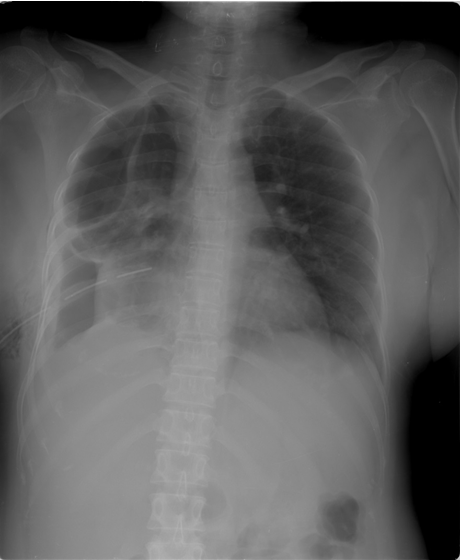

A 35-year-old Indonesian mongoloid female patient presented with a painful lump in her left leg. She had history of lump in her left leg since seven years prior to admission. Initially, the lump was only 1 cm in diameter. There was no history of trauma. The patient was initially treated by general surgeon, and had undergone excision of the lump. After the surgery, recurrence occurred and the lump developed gradually. Within seven years, the patient did not routinely visit hospital to have the condition of the lump checked. One week prior to admission, the patient complained about difficulty in breathing. She came to a primary hospital and was found to have a pleural effusion in her right lung and chest tube was inserted. She was then referred to our hospital. On the physical examination, a 10x10x5 cm hard tender mass was found in the left lower leg (Figure 1). Range of movement (ROM) in the left knee joint was full, but in the ankle joint, the ROM was limited. Laboratory results including tumor marker were unremarkable. Plain radiograph of the left leg showed lytic lesion in diaphysis and metaphysis of the left tibia with osteodestruction of tibia and extension to the surrounding soft tissue (Figure 2). A chest radiograph was performed (Figure 3) which showed bullae in the superior lobe of the right lung, pneumothorax, fibroatelectasis in the middle lobe of the right lung, and right pleural effusion. A chest MSCT showed hydropneumothorax and multiple bullae of the right lung and solitary nodule in the left lung suspected to be a distant metastasis from the primary tumor site (Figure 4). The patient was assessed with hydropneumothorax of the right lung caused by possible malignancy. A fine needle aspiration biopsy (FNAB) of the lesion in the left leg then performed with the result of clustered tumor cells within a group, with small cells with atypia, small amount of cytoplasm, spindle nucleus with hyperchromasia with background of lymphocyte and erythrocyte (Figure 5). A clinicopathological conference was then arranged with a recommendation of transfemoral amputation. A transfemoral amputation was then performed and the histopathological result showed a pattern of epithelial tumor with solid arrangement and infiltration to surrounding tissue, including to the upper dermis. The observation of the cells showed small to moderate cell sizes, small amount of cytoplasm, round to spindle nucleus with small amount of mitosis. The conclusion of the histopathological examination was islands of epithelial cells in a densely-populated stroma of spindle cells suggesting adamantinoma (Figure 6). The positive cytokeratin was found in the immunohistochemistry on the tumor cells and it was also relevant with the diagnosis of adamantinoma (Figure 7). | ||||||

The symptoms initially present with nonspecific characteristics and its variety of the symptoms is related to location and extent of the disease. Pain is the most common clinical manifestation reported. It was in accordance to this case where the patient was presented with painful lump on her left lower leg. The onset of the clinical sign and symptom is insidious with slow and progressive characteristic. The patient usually tolerates symptoms for many years before seeking medical attention because of this characteristic of clinical manifestation as seen in this patient [5]. However, some of the patients present with swelling with or without pain as local swelling being the second most common symptom to appear. In addition, this case also showed that involvement of the anterior tibial surface can produce bowing of the tibia [6]. Based on radiographic assessment, adamantinoma is an osteolytic type with mono or multi-loculated lesions. In accordance to its benign characteristics, it is well circumscribed with septa and a peripheral condensation may appear. It is usually appear in the diaphysis or metaphysis of the anterior tibial. The lesion usually grows intracortical and it may spread longitudinally. However, it does not rule out the possibility of cortex destruction and marrow cavity invasion of the tumor [7]. The MSCT examination could reveal the characteristics of the lesion better than plain radiograph and can also detect another tumor site invisible on plain radiographs. The differential diagnosis based on plain radiograph examination including fibrous dysplasia and osteofibrous dysplasia [2]. . The patient in this case had tumor in her left leg which develops progressively after the first excision seven years ago. This might be due to inadequate attempts of removal where incomplete resection may result in higher recurrence rate up to 30% in the period of 85 months. Therefore, adamantinoma is suggested to be treated with wide surgical excision and reconstruction or amputation since its likelihood of healing is high subsequent to radical treatment [2] [3]. If early diagnosis is successfully made, wide local excision with a substantial margin of normal bone is still acceptable [8]. However, if there has been more than one recurrence or in large tumor with extension to the surrounding soft tissues, radical resection or amputation is advisable as shown in this patient where knee amputation was performed [9]. Adamantinoma is a low-grade malignant tumor of epithelial origin which metastasizes late. This tumor is insensitive to radiation and has capabilities of metastasis, especially to the lung. [8]. Metastases including in lung or lymph nodes are rare and can occur in 10–20% of patients. Pulmonary metastases are more common that regional nodal metastases from this tumor. It is not uncommon to develop distant metastases even up to 10 years after detection of the primary [3] [5]. This was in accordance with this case, where the main reason to seek medical management was due to difficulty in breathing and it was correlated with repeated local recurrences that might be due to inadequate primary excision of the tumor. However, it is difficult to evaluate its true metastatic potential due to several reasons such as long term follow-up, low number of the case, and slow growing nature of the tumor [5]. Several reports in literature have described metastasectomy for pulmonary lesions in both curative and palliative settings with good results. Mean survival of patients with metastatic disease is reported to be 12 years. There appears to be no definitive role for radiotherapy or chemotherapy [10]. Due to its excellent prognosis, it is crucial to diagnose this rare bone tumor in the early stage. It can be achieved by histologic examination, where this tumor can be distinguished easily. However, not only this tumor is rare, the heterogeneity of the tumor presentation may lead to confusion in some cases. On the histologic examination with inadequate sample taking, epithelial component may be seen only focally in the differentiated adamantinoma case, therefore in some cases, extensive sampling of the tumor is mandatory [11]. The challenge in making diagnosis and preparing proper management emphasizes that clinicopathological conference among orthopedic surgeon, pathologist, and radiologist was very important to ensure the patient get the best treatment available in musculoskeletal tumor cases. At the moment where the diagnosis is certain, resection with wide surgical margins or amputation can be applied to the patient.. | ||||||